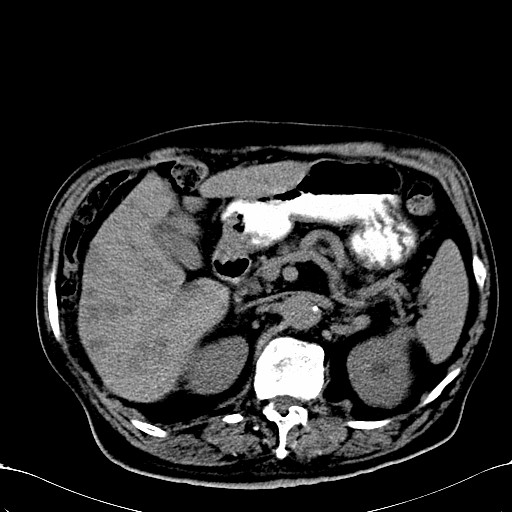

标题: CT28270:胰管扩张,肝多发占位 [打印本页]

标题: CT28270:胰管扩张,肝多发占位

患者,男,75岁。

考虑胰腺钩突癌并肝内转移,建议强化明确。

1)考虑胰头癌并肝脏多发性转移;建议行ct增强扫描检查。2)胃窦癌?建议行胃镜检查。

肝脏多方低密度结节,边缘模糊,考虑多发转移,胰管明显扩张,建议增强扫描钩突情况

肝脏多发低密度灶,胰头似呈低密度,胰管扩张,建议增强,

胰管显著扩张,但胆总管未见扩张征象,不太符合胰头占位!考虑慢性胰腺炎.胃窦占位并肝内转移可能!mrcp胃镜增强一起上!